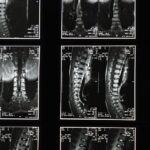

Quels examens permettent de diagnostiquer un pincement discal?

Une IRM ou une radiographie est souvent utilisée pour confirmer le diagnostic d’un pincement discal ou d’un disque écrasé.

Une IRM ou une radiographie est souvent recommandée pour évaluer l’état de la colonne vertébrale.